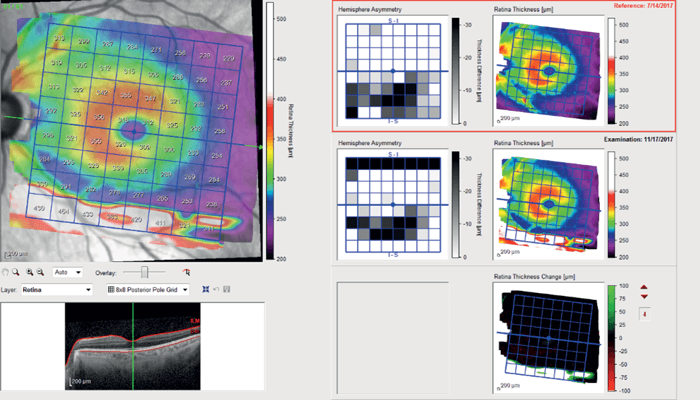

OCT-RNFL in the left eye showed only mild thinning inferotemporally (see Figure 4) and OCT Macula showed asymmetry of retinal thickness with inferior thinning (see Figure 5).